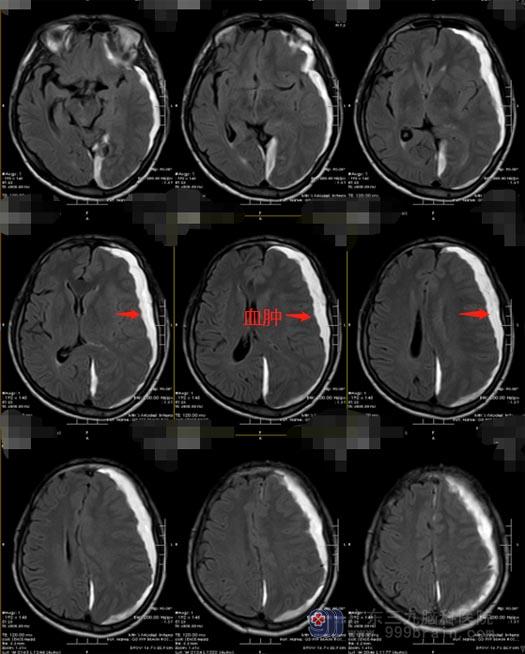

恰巧,陈先生在广州工作的亲戚回家省亲,听闻陈先生的事情后,建议他转至上级医院。他们连夜自驾车十几个小时将陈先生送到广东三九脑科医院。急诊入住神经外五科后,立即复查了头颅CT,显示:1.左侧额颞顶枕硬膜下亚急性血肿;2.左侧枕部大脑镰血下积血;3.创伤性蛛网膜下腔出血;4.右侧颈内动脉虹吸段钙化灶。

慢性硬膜下血肿的形态非常有特征性,其形态如新月,见到脑内出现“新月”,基本上确定为本病无疑了。慢性硬膜下血肿是发生在硬脑膜和蛛网膜之间的血肿,是非常普遍的神经外科疾病,早期症状不明显,CT常出现少量蛛网膜下腔出血,患者主要表现为慢性颅内压增高症状、神经功能障碍以及智能和精神症状,可伴有头痛偏瘫,也有一些患者无自觉症状,当血肿累积到特定量可能会危及患者生命。